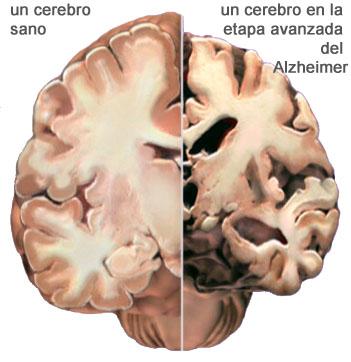

En un formato breve: en el estudio, coordinado desde el Instituto de Neurociencia de Grenoble, Francia, con participación española, se describe qué provoca en las fases tempranas del alzhéimer la pérdida de dinámica y posterior deterioro de las espinas dendríticas, los compartimentos neuronales encargados de recibir los impulsos nerviosos de otras neuronas.

Se ha encontrado una relación entre la presencia de los ya famosos péptidos beta-amiloide –la marca de la casa del Alzheimer- y la rápida pérdida del dinamismo del citoesqueleto de la actina de las espinas dendríticas mencionadas anteriormente. El citoesqueleto es un entramado tridimensional de proteínas que provee de soporte interno a las células siendo, los filamentos de actina, uno de sus componentes.

Esta menor dinámica hace que la transmisión de la información no se realice como debiera, lo que finalmente, provoca la pérdida de las espinas y, por tanto, de la capacidad sináptica de las neuronas.

Lo importante, dicen los autores, es que, en las primeras fases de la enfermedad, estos daños estructurales podrían prevenirse, siendo un obligado tema de investigación en el presente para obtener posibles nuevos medicamentos, en el futuro.